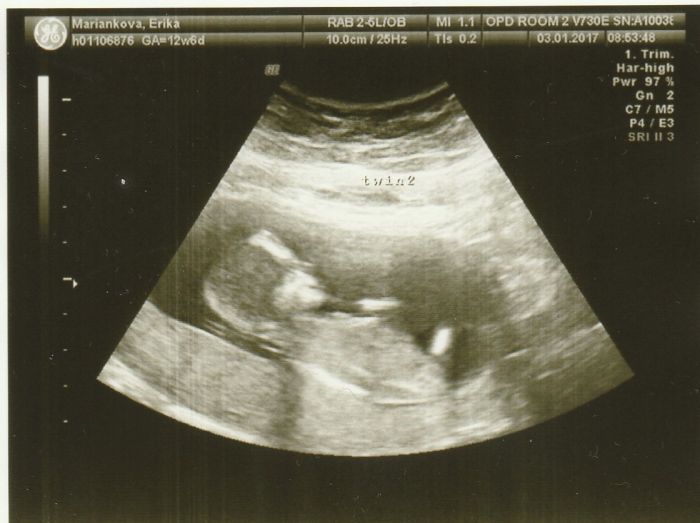

[967603] Som uz davala davnejsie, ale pridam teda este raz

dalsi utz mam az 24.2 a uz sa neviem dockat

Seiko krásné fotecky,hlavně ta druhá kde jsou obě miminka

je to krásné to takhle vidět